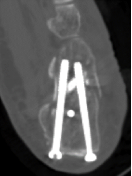

回到前文所述的患者程某,其X线片及CT检查提示其骨折系波及关节面的严重粉碎性骨折,具有明确的手术指征。

在骨科中心主任吴超的带领下,团队采用了天玑Ⅱ骨科手术机器人为程某开展了微创手术治疗,该手术时间短、创伤小、出血少、透视次数少,同时实现了骨折块的解剖复位和精准的螺钉置入及固定;术后影像学显示患者关节面完全复位,螺钉位置良好,固定可靠。